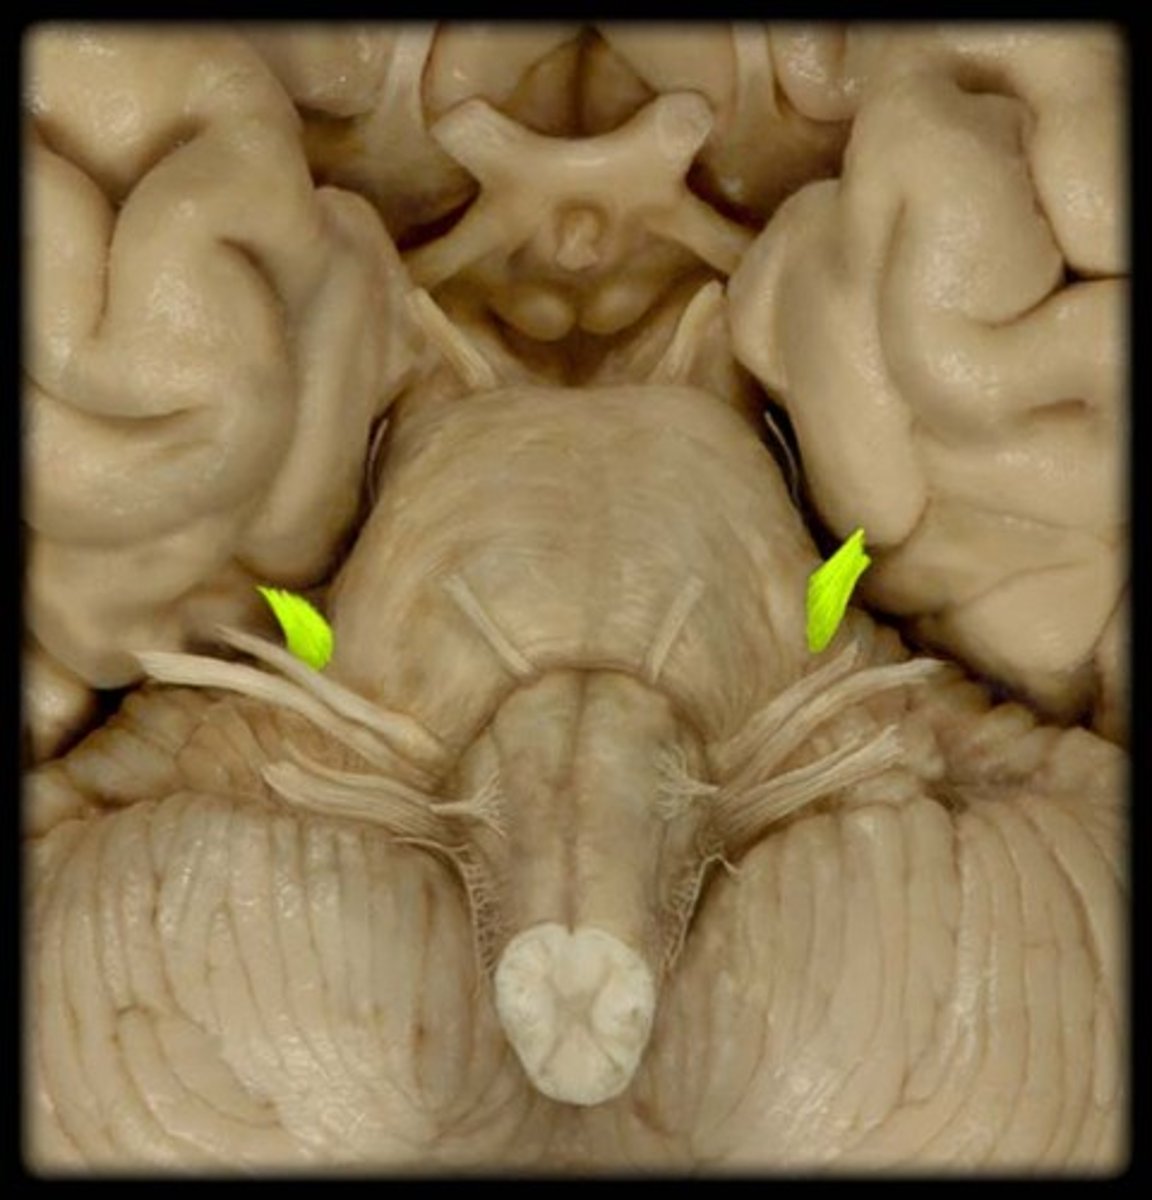

IV Trochlear

motor eye movement